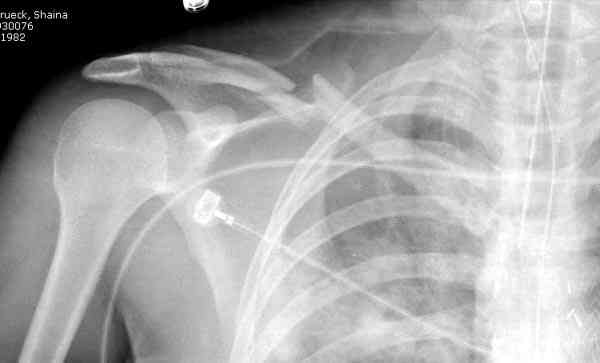

Второй случай тоже недавно оперирован по поводу

ложного сустава, в марте травма, через 4.5 половиной

операция..

Описанный случай это больная моего партнера, мы недавно случай разбирали на нашей конференции (Morbidity and Mortality Conference аналог клинического разбора)

Выставлен как пример, к чему может привести

неудачно выбранный фиксатор.